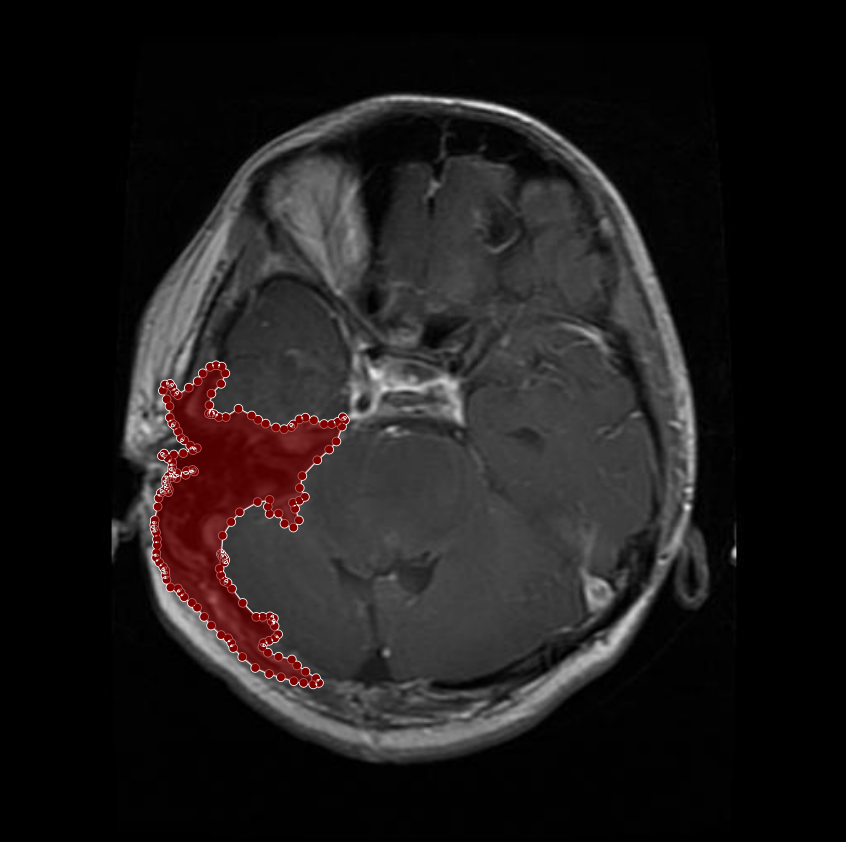

Figure 5: Samples of whole-region misannotations. The red area indicates regions that were initially marked as tumors but were identified by radiologist and physician as non-tumorous.

In some cases, regions initially annotated as tumors were later identified by physician and radiologist as non-tumorous. These corrections were essential to avoid false positives that could mislead model training. An example of such a case is shown in Figure 5, where an area initially believed to be a tumor was excluded from the final annotation after expert review.